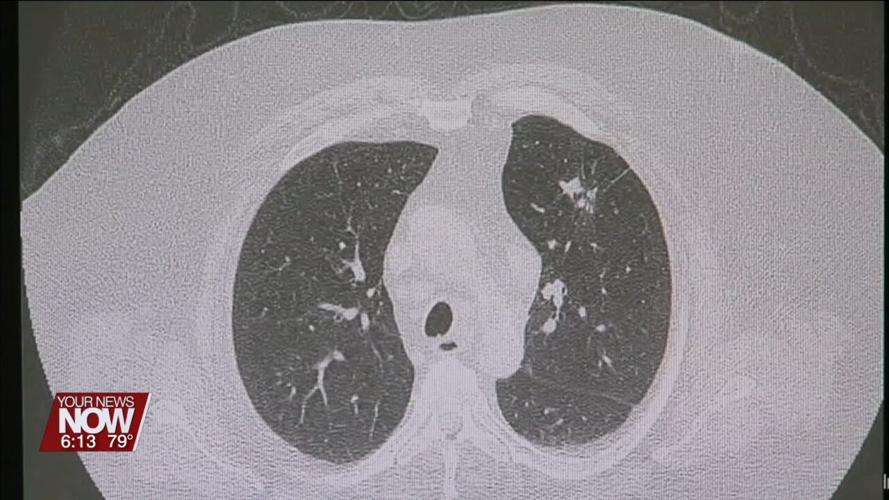

But doctors say that fear shouldn't stop a person from getting screened – especially if it can save their life. Right now, lung cancer screenings are recommended annually for adults between 50 and 80 years old who have a 20-pack-year smoking history and currently smoke, or have quit within the past 15 years. For those unfamiliar, a lung cancer screening is non-invasive and involves a CT scan which creates a detailed X-ray of the lungs. And while smoking is the leading cause of lung cancer, there can be other risk factors too. For example, lung cancer can run in a person's family or they could be exposed to something environmental like radon.

"If you are in that group that would qualify for a screening, I would certainly recommend that. So we have a chance to find any possible disease early. And by the way, most nodules or spots we find in the CT scan done for screening, they're actually benign. So often we just monitor them," commented Dr. Humberto Choi, Cleveland Clinic.